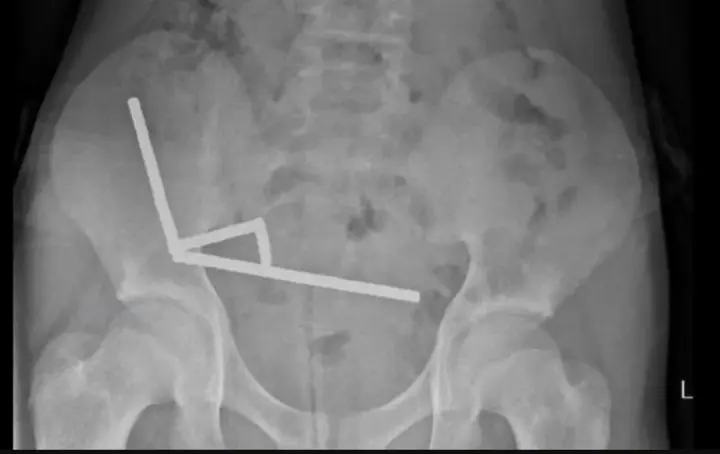

В Новой Зеландии 13-летнему мальчику провели сложную операцию после того, как он проглотил до 100 неодимовых магнитов, купленных через интернет. Магниты слиплись внутри кишечника, образовав четыре металлические цепи, что привело к повреждению тканей.

Инцидент произошел на Северном острове, в городе Тауранга. Через четыре дня сильной боли мальчика госпитализировали. Хирурги больницы извлекли магниты вместе с частями поврежденного кишечника. После восьми дней лечения ребенка выписали, сообщил New Zealand Medical Journal.

По данным врачей, подросток проглотил около 80–100 магнитов размером 5×2 мм, предположительно, "играя или из любопытства". Такие магниты запрещены к продаже в Новой Зеландии с 2013 года, однако их до сих пор можно приобрести на онлайн-площадках, несмотря на предупреждения правительства об опасности.